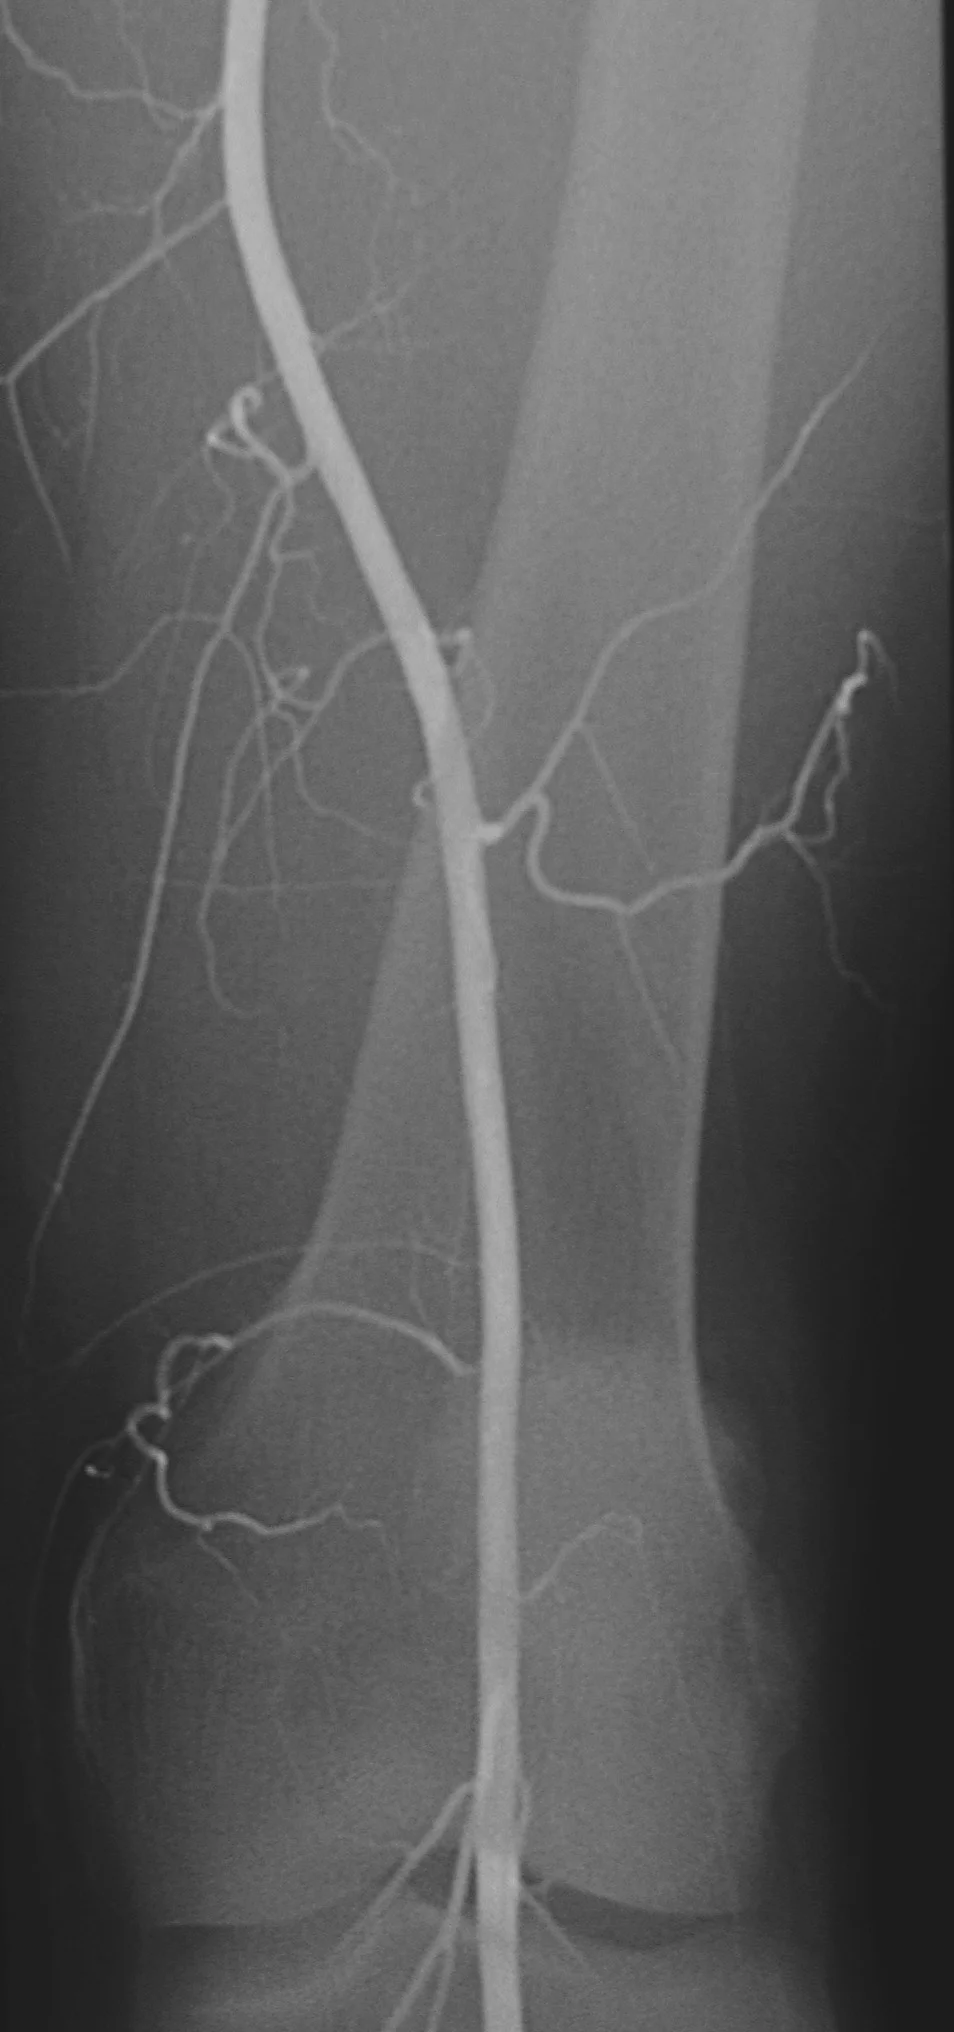

38 year old male with a history of smoking and no history of diabetes, hypertension, or hyperlipidemia who presents with cold and painful feet.